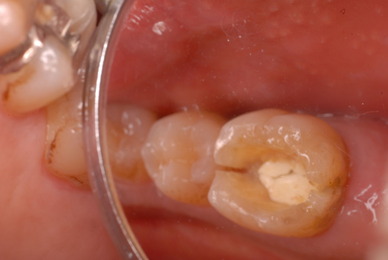

これぞ医師の姿ではないでしょうか。![11229551_834920046584649_8659418848563116234_n[1]](https://livedoor.blogimg.jp/netdental/imgs/c/0/c098deb4.jpg)

![11053897_834920076584646_6691737990508884178_n[1]](https://livedoor.blogimg.jp/netdental/imgs/b/b/bb679b8f.jpg)

![11010956_834920133251307_8897824032330972564_n[1]](https://livedoor.blogimg.jp/netdental/imgs/c/2/c2aa3129.jpg)

![10403096_834920093251311_4823181277198290695_n[1]](https://livedoor.blogimg.jp/netdental/imgs/b/7/b77edc79.jpg)